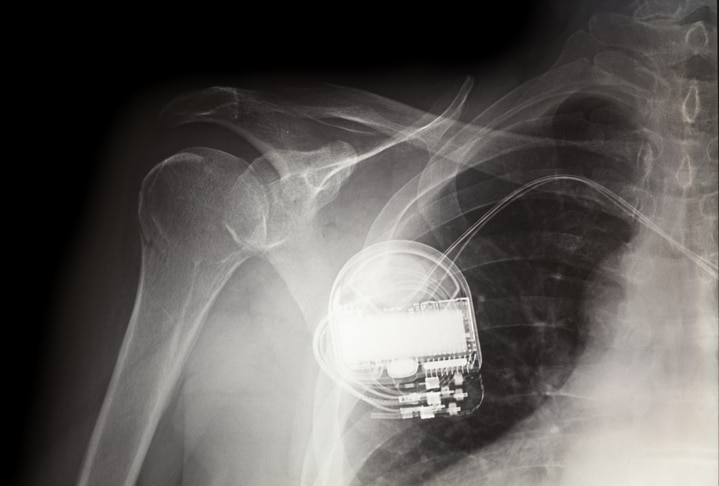

Modern pacemakers are smaller than a matchbox and can be implanted under the skin while a patient is awake.

When Deborah arrived at Methodist Charlton by ambulance, tests revealed she had suffered a heart attack, and her heart rate had dropped to a dangerously low rhythm. Doctors recommended a pacemaker, which would keep her heart beating steadily.

“She developed slow heart rates that resulted in symptoms of lightheadedness and fatigue,” explains Amit Guttigoli, MD, cardiologist on the medical staff at Methodist Charlton.

Dr. Guttigoli told her she would need to stay awake while he implanted the pacemaker.

Dr. Guttigoli says the procedure is quick and simple, with patients under moderate sedation: “Quite often, patients are awake and talking.”

Deborah recently received a new pacemaker after doctors noticed the battery had run low.